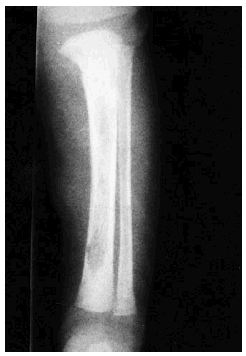

Se realizó biopsia de uno de los tumores que mostró una lesión nodular bien definida, no encapsulada, localizada en la dermis y respetando la epidermis (fig. 2). La parte periférica de la lesión se componía de fascículos compuestos por células fusiformes, de amplio citoplasma eosinófilo y con núcleos alargados. En el centro de la tumoración se encontraban cúmulos de cé-lulas redondeadas o poligonales, con citoplasmas de bordes mal definidos y núcleos hipercromáticos. Esta zona mostraba espacios vasculares con luces interconectadas en un patrón en «asta de ciervo» (fig. 3). La inmunohistoquimia demostró positividad para vimentina y actina específica del músculo. Se practicó hemograma y bioquímica sérica, que fueron normales. La radiografía de tórax, la ecografía abdominal y cardíaca y la tomografía axial computarizada (TAC) cerebral no detectaron anomalías. En la serie ósea se detectaron múltiples imágenes líticas diafisometafisarias en fémures, tibias y húmeros, así como en mandíbula y pelvis, con bordes bien definidos no escleróticos (fig. 4). Se realizó una interconsulta a Neurología solicitando valoración de la parálisis facial, y ésta fue etiquetada de parálisis facial periférica de etiología probablemente obstétrica.

Fig. 4.--Imagen lítica en la tibia.